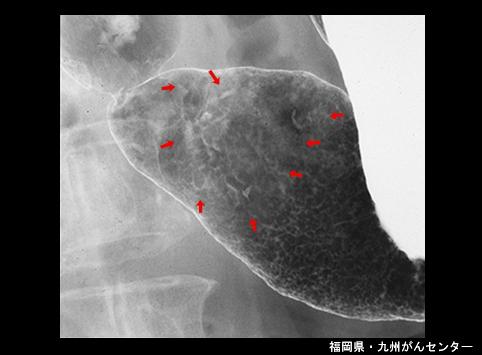

Criteria of Hist.ClassificationMalignant epithelial tumor/Adenocarcinoma

LocationStomach/Antrum

Technique, MethodX-ray

Macroscopic TypesType 0/IIc (IIc+IIb) Superficial depressed and flat type

Size40 -

Depth of Tumor Invasionmucosa